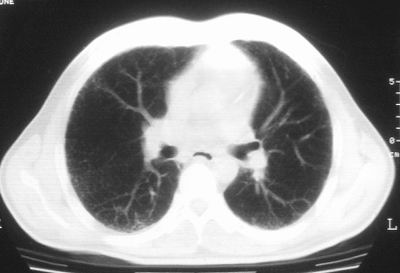

双肺散在小结节影,考虑粟粒性肺结核.肺窗薄扫会更好看些.

双肺外侧带胸膜下可见网状阴影,考虑轻度肺间质纤维化。

双肺纹理增强并可见网格状影达外带,考虑双肺感染并轻度间质纤维化

考虑肺间质纤维化伴肺部感染.